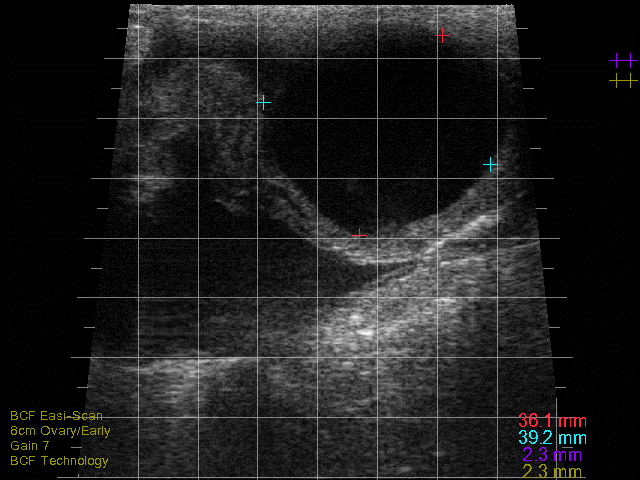

Detailed ultrasonography can detect pregnancy from 22-24 days post-insemination but due to higher rates of loss and inconsistency in quickly detecting the foetus, it is advisable that ultrasonographic pregnancy diagnosis at 28-30 days post-insemination is performed as it becomes very reliable (see Photo 2)2. At this point, the embryo becomes visible as a small, echogenic (white) structure suspended within the black (anechoic) uterine fluid2. Beyond this point, ageing is performed by either measuring or ‘eyeballing’ foetal crown-rump length, head or trunk diameter, head length or eyeball diameter (for references lengths see Table 1)6,7. Modern ultrasound machines will automatically give an estimated days in-calf, if the image is frozen and a distance is measured, but the author finds that the grid function (where a box represents 10mm) is a more useful way to eyeball these measurements without having to freeze the image. Thus thinking in boxes allows the user to reliably age using the crown rump length up to day 60 and then using head diameter and/or eyeball from days 60-150 days (see Photo 3). Measuring the placentomes is not a very reliable method to accurately age owing to the fact that placentome size will vary depending on where in the horn it is located, with smaller placentome being at the edge of the horns2.